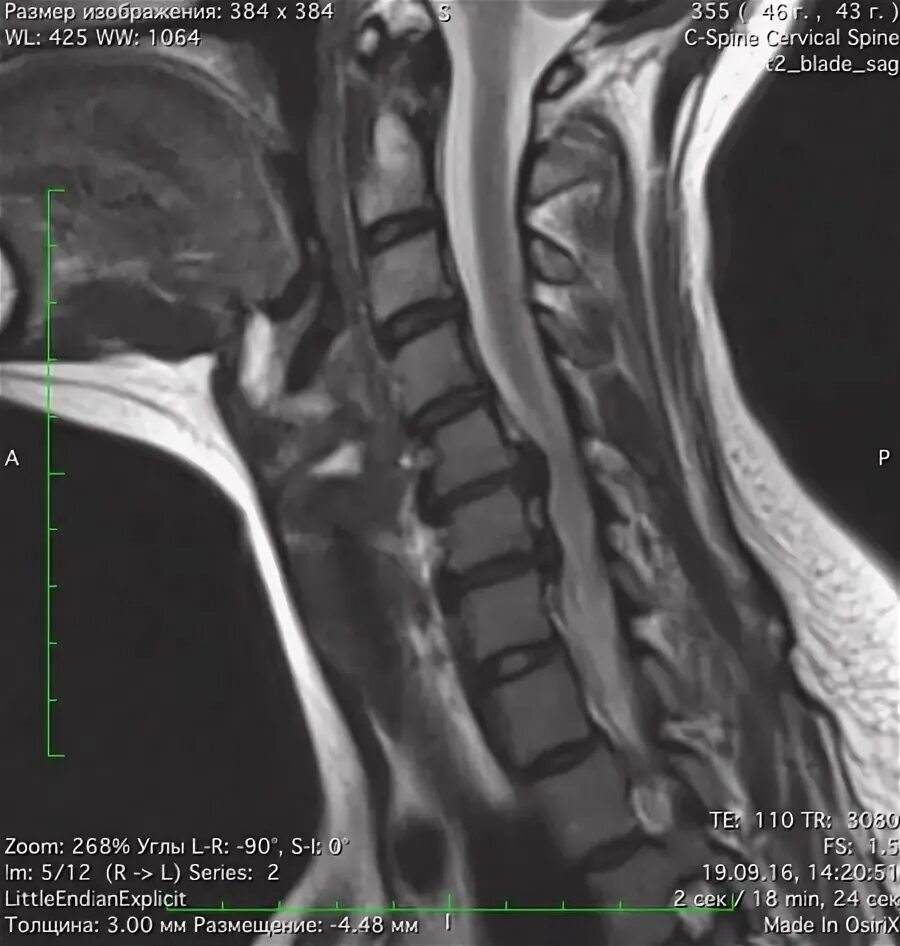

Протрузии дисков c6